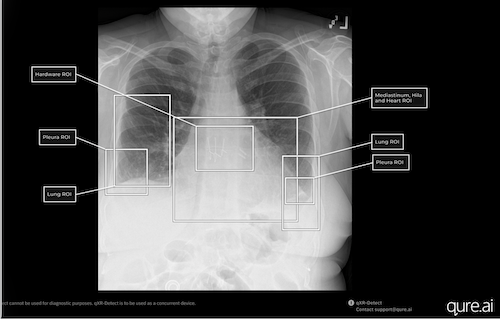

Qure.ai qXR-Detect provides bounding boxes and indicates the location of suspicious regions of interest. Photo: Qure.ai

Chest radiography is the most performed imaging exam today in the US, with 70 million obtained each year in the ER, outpatient department or part of routine health assessments. This "6 in 1" indication FDA clearance, completes the entire qXR product suite of AI algorithms, covering the breadth of findings encountered on chest X-rays. Findings that can be categorized into six regions of interest are added including — lung; pleura; mediastinum /hila & heart; bone; hardware and others.

“There are more than 100 potential findings on a plain film chest X-ray that AI tools can help detect and assist radiologists with, supporting earlier recognition of abnormalities,” states Professor Amit Gupta, Division Chief of Cardiothoracic Imaging and Modality Director of Diagnostic Radiography at University Hospitals Cleveland Medical Center. “Tools such as qXR-Detect go beyond binary detection alone. In addition to flagging potential abnormalities, the system provides visual localization and explainability, such as through bounding boxes and region-of-interest labels, which helps the interpreting radiologist quickly understand where and why an alert has been generated. When used alongside standard clinical interpretation, chest radiography augmented with AI-based detection and localization can offer a practical frontline support tool for identifying findings such as lung nodules and other abnormalities that may warrant closer attention or further diagnostic workup.”